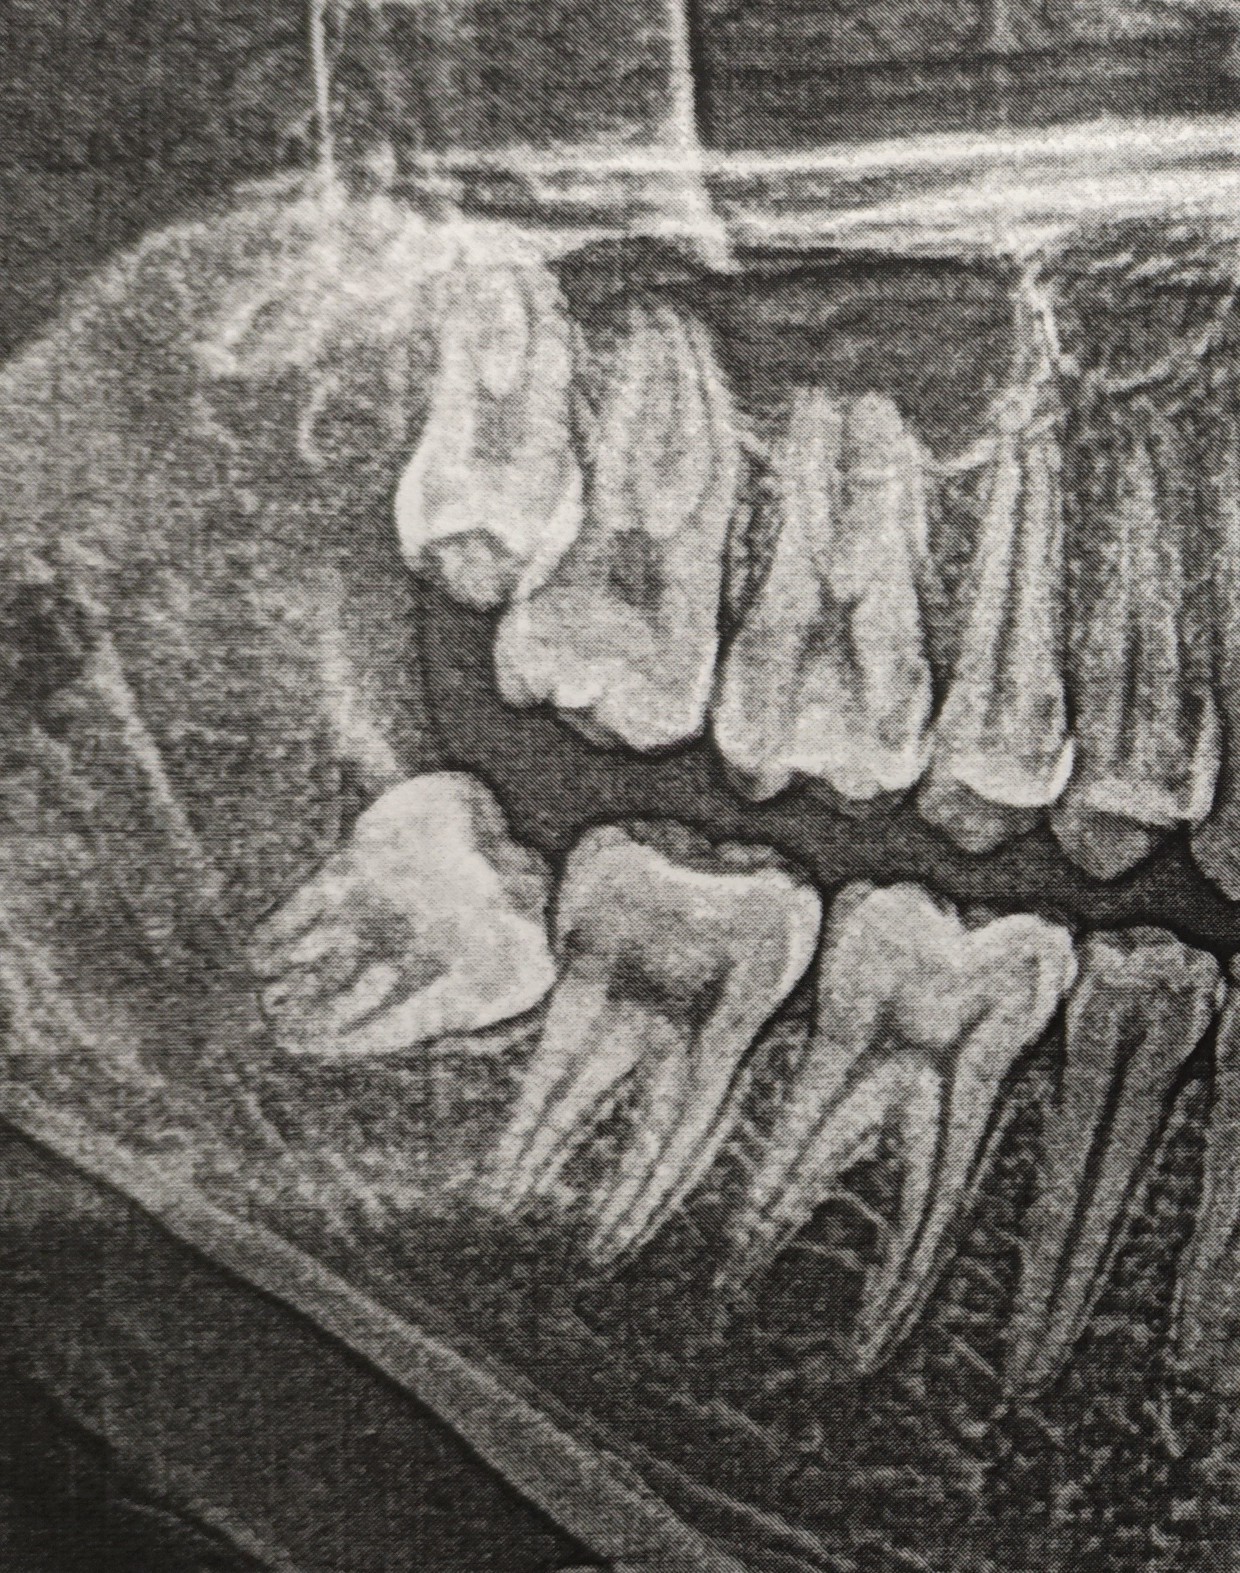

Прошёл еще месяц. То самое «темное пятно» начинает постепенно «белеть», а ведь прошло всего 2 месяца со дня удаления.

Красными стрелками я отметил постепенное «появление» периодонтальной щели. Вон та черная полоска (пространство) между корнем зуба и костной тканью. Грубо говоря, там связка, которая выполняет опорно-удерживающую функцию, что позволяет зубу несколько амортизировать при жевании.

Следующий визит был запланирован через три месяца. Итак, новый снимок:

На данном снимке видно, что область удаления продолжает восстанавливаться, всё четче видны очертания нижнечелюстного канала, в котором проходит одноименный нерв.